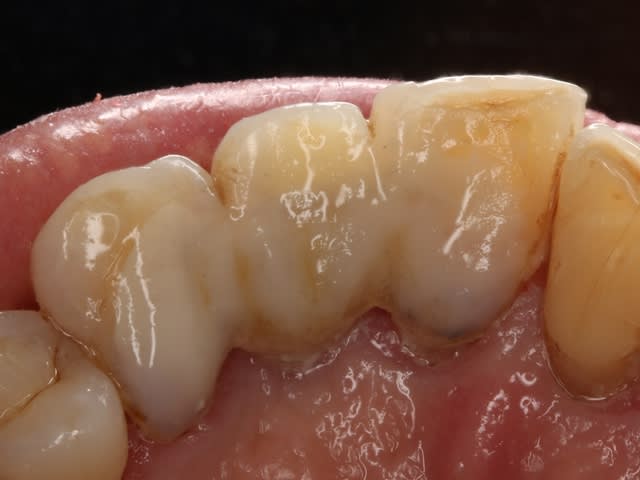

Tiens belle maman est passée au cabinet ce matin, j'avais déjà parlé d'un bridge collée réalisée en Vectris/Targis (du composite et une armature en fibre de verre: un produit Ivoclar des années 90). Voici des images au bout de 3 ans de collage.

Bridge vectris hnvdsj - Eugenol

Bridge vectris 1 gdoui3 - Eugenol

Bridge vectris 2 ccew9j - Eugenol